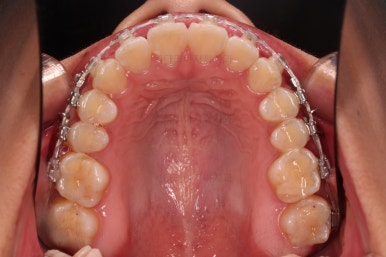

1. 초진 시 입안의 모습 평가

부산연산역치아교정 키다리아저씨치과에 처음 내원했을 당시의 입안의 모습이비다.

앞니 약간, 어금니쪽 약간 삐뚤어진 것, 그리고 위아래 앞니가 약간 뻗쳐 보이는 양상 이외에는 매우 가지런해 보여서 교정치료를 굳이 왜 하시려고 하지? 라고 생각될 정도의 치열 상태였습니다.